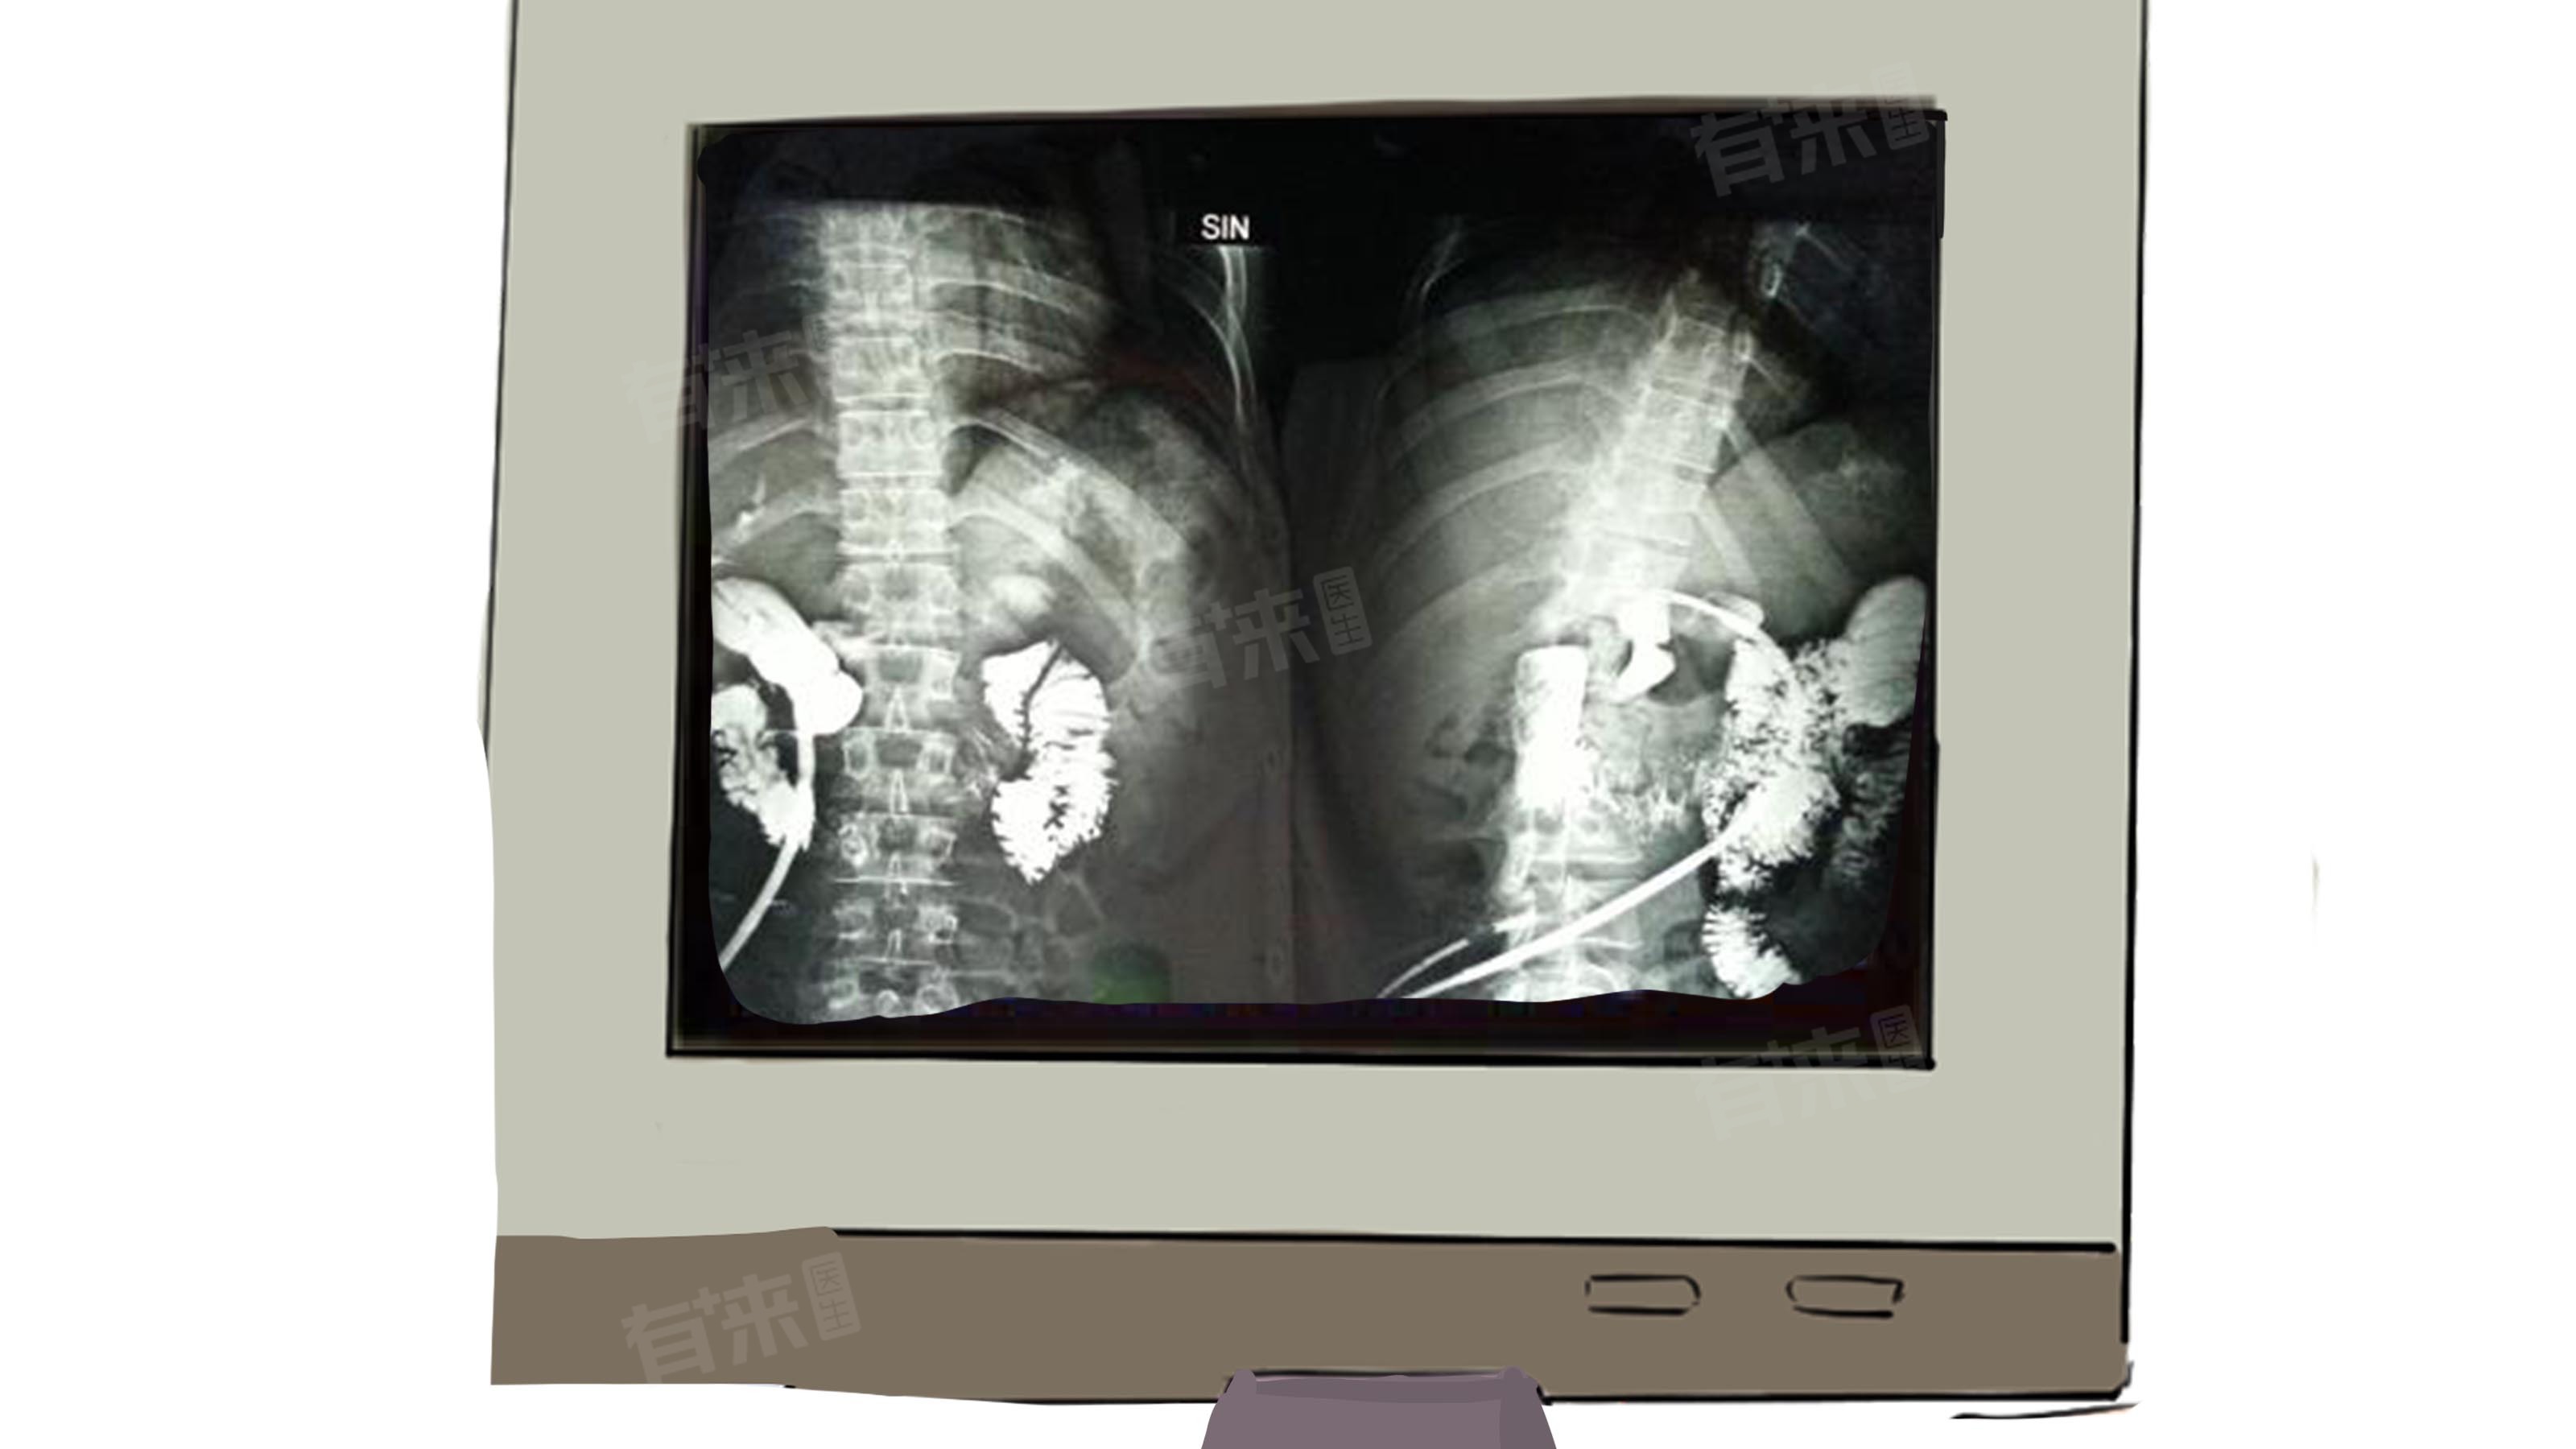

- 为后续治疗提供通道:T管为后续的胆道镜治疗、胆道造影等提供了出入口,方便医生进行进一步的检查和治疗。如果在手术过程中结石无法取出或有胆管的残留结石,还可以通过T管形成的窦道,置入胆道镜,将胆管内的残留结石取出,作为二次治疗的通道。